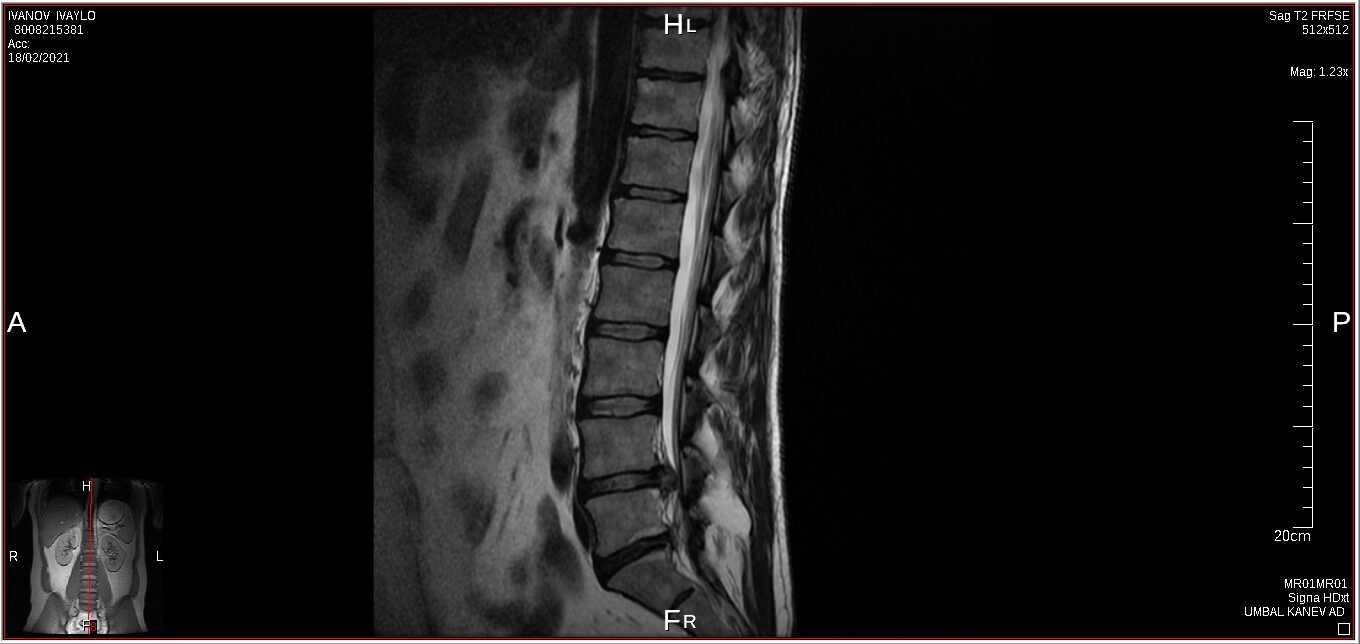

I have a lower spine problem, herniated disk and was using acupuncture (acupuncture is really good to control your musculus and controlling you like a robot) treatments with a Chinese doctor, first time all was perfect, but second time looks like happen mistake, you will be able to see this on pictures from private MRI scan– nuclear magnetic resonance that I have organised for myself. My left leg was just bone and skin, I lost all the musculus, because was not able to feed the main nerve responsible for keeping the proper function of the whole leg – I was parallelized. Pain is 24/7, 10 out of 10. At Royal infirmary hospital Edinburgh where I was hospitalized was giving me crazy amount of pain killers and very strong, that never helped. The doctors at the hospital they did great job providing me with modern technology to prevent the rest of the disk to slipping out to obtain the so-called calcification. All NHS staff did great job looking after me there. By 98% of the Doctors from around the world that I have managed to contact told me, that I have to make operation and there is no chance this to be sorted out other way. Well I have spent six months from my life and thanks god I had the finance to do that, trying to avoid operation. I have meet the right people to help me and expand my knowledge and I managed to avoid operation. Thanks to nature too. This situation get me to start learning a lot for human being anatomy and physiology, also reflexology, trigger points, blood, tocsins, minerals, how brain is responsible and reacting and much more…